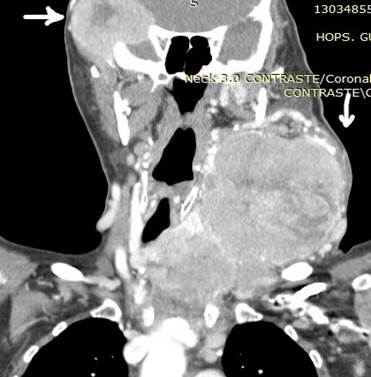

CASO 2 (METASTASIS CEREBRAL)

Paciente de 68 años de edad, que ingresa referida de otra institución por presentar más tumoral en región occipital derecha de gran tamaño dura muy adherida, dolorosa con circulación colateral; paciente desorientada en tiempo y espacio, irritable y poco colaborativa, en algunas ocasiones ha presentado convulsiones tónico clónicas. Además, presenta masa cervical voluminosa, a nivel tiroidea, dura, adherida a estructura aéreas y vasculares.

Se toma biopsia con aguja gruesa de lesión tumoral cervical y tumoración occipital encontrando carcinoma papilar variante oncocitica. Paciente fue tratada por el departamento de oncología clínica en forma paliativa y con Sorafenib por no haber mejoría con radio-yodo.

Ilustración 6 Metástasis ósea y cerebral con gran vascularización.

![]() |

Fuente: Hospital de Especialidades Guayaquil “Doctor Abel Gilbert Pontón”.

Autor: Dr. Fernando Moncayo A.

Ilustración 8 Ca de tiroides y metástasis cerebral.